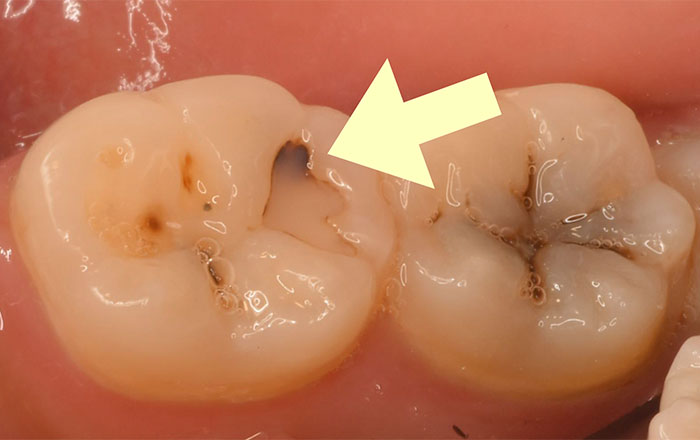

軽度のむし歯の状態(C1)は、痛みなどの症状はありませんが、歯の一番外側にあるエナメル質が溶け始めている状態です。

この段階のむし歯の治療方法は、

①むし歯の部分を削る

②歯科用プラスチック剤(コンポジットレジン)を詰める

③光を照射し、プラスチック剤を固める

という処置をします。